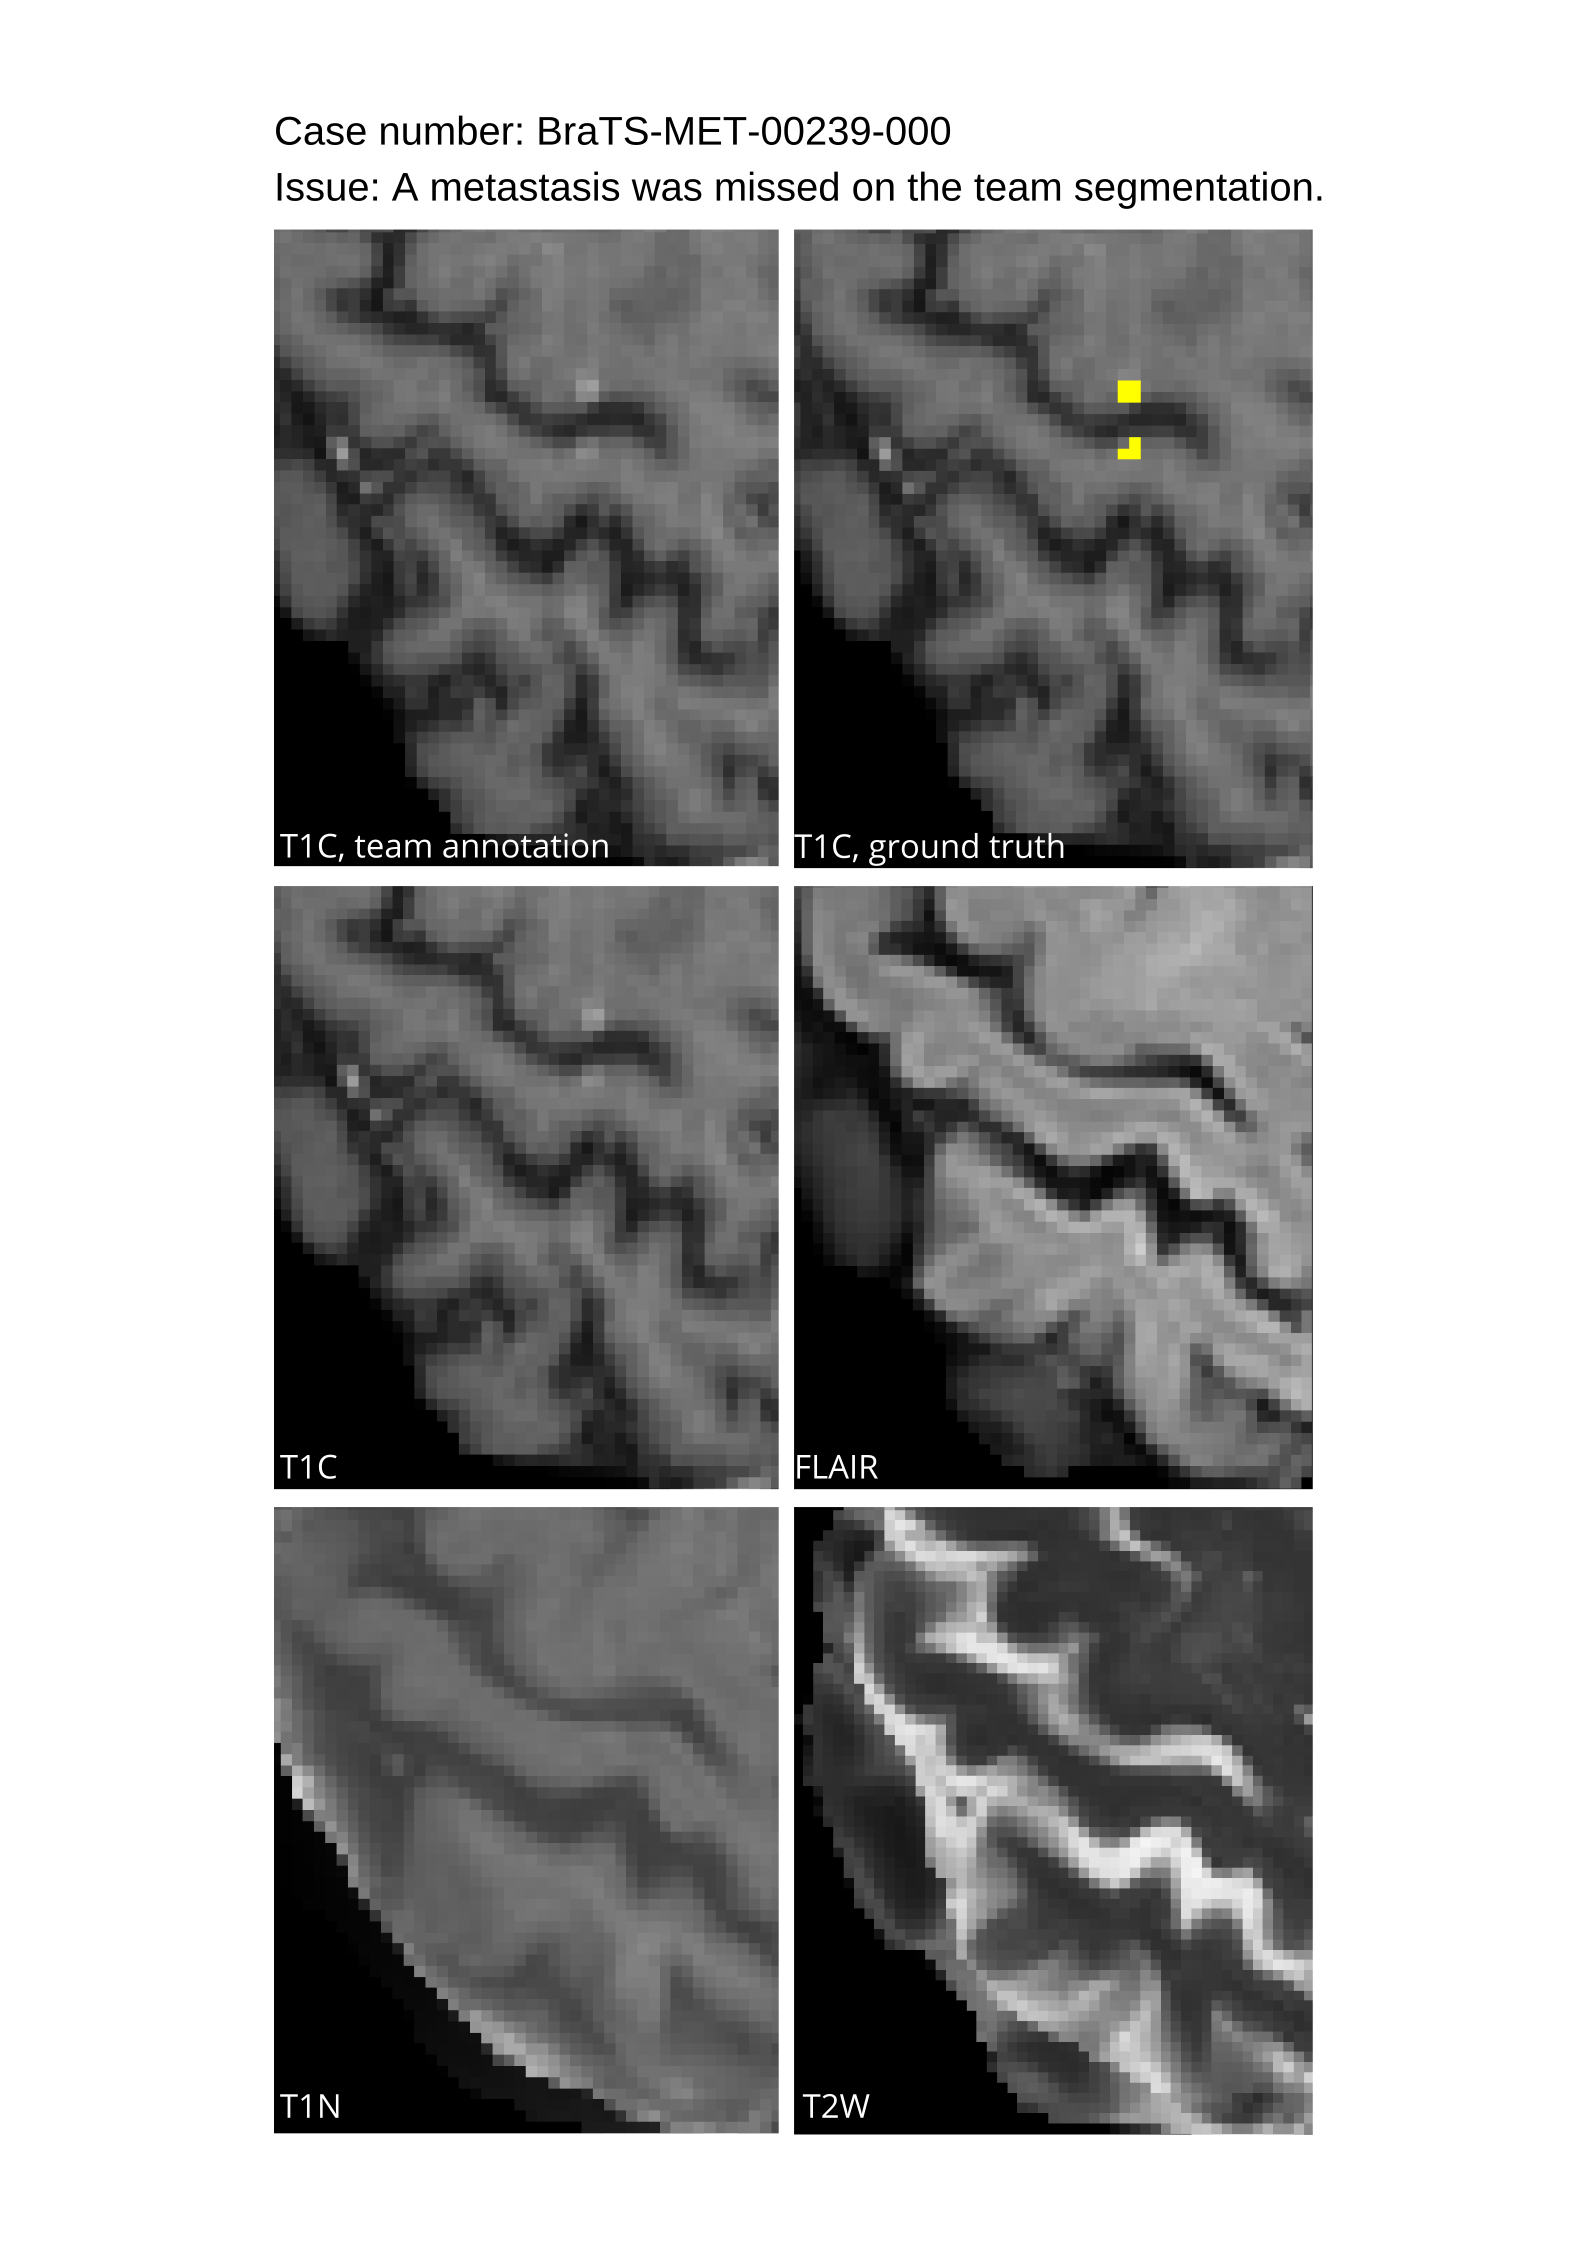

4.9 Common Errors of Automated Segmentations

Based on observations from previous BraTS challenges, common errors in automated segmentations were identified. The most typical errors in the current challenge included:

1. 1.

Automated algorithms missing small metastases. Enhancing metastasis was fused using the minority voting algorithm to aggregate all enhancing tumor voxels identified by the three algorithms. However, many small metastases were missed and were manually segmented by neuroradiology attendings.

2. 2.

Segmentation of white matter changes from microvascular disease. Peritumoral edema segmentations were checked by neuroradiology attendings and modified.

3. 3.

The segmentation of non-enhancing lesions that have intrinsic T1 hyperintensity. Voxels with intrinsic T1 hyperintensity were manually removed from ET segmentations.

These insights led to specific adjustments in the annotation process to enhance accuracy.